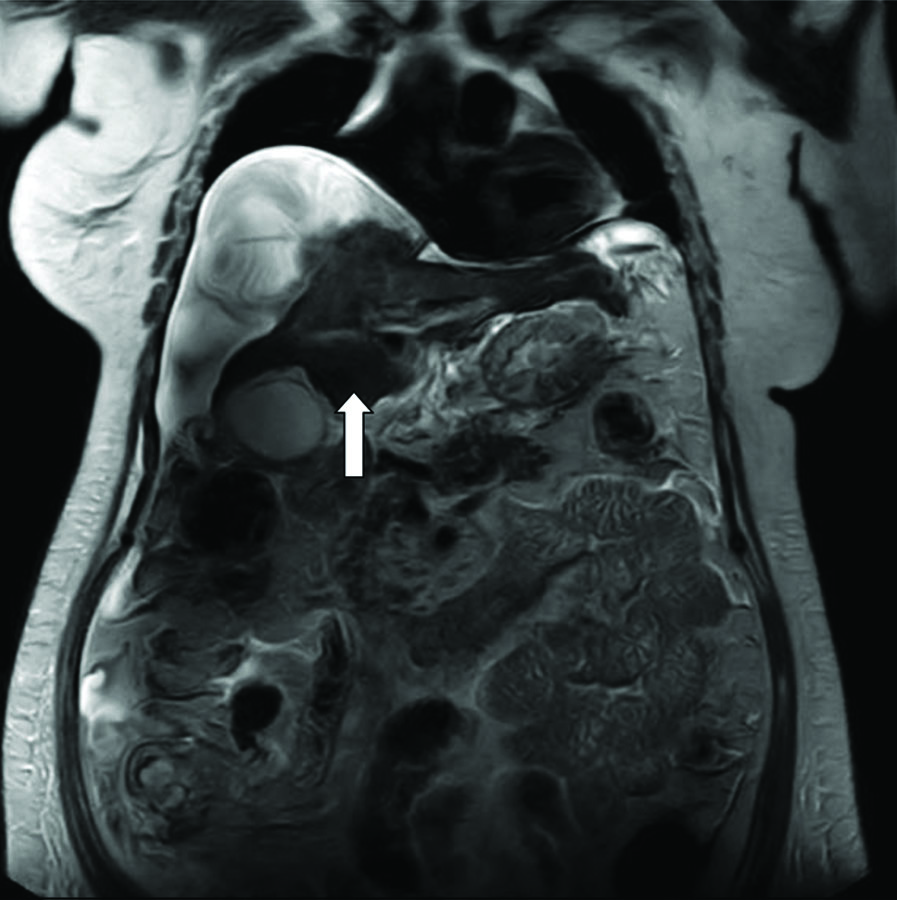

Magnetic Resonance Imaging (MRI)-Magnetic Resonance Cholangiopancreatography (MRCP) suggested chronic liver disease with ascites and revealed T2 hypointense-dependent content in the gall bladder, which may represent concentrated bile, sludge, or microlithiasis. The patient was planned for a triple-phase Computed Tomography (CT) scan, but it could not be done due to raised creatinine [Table/Fig-3]. Blood culture revealed growth of Citrobacter freundii, and urine culture showed growth of E.Coli and Klebsiella pneumonia. Consequently, the patient was started on antibiotics. Although the patient’s sensorium fully recovered, kidney function tests remained deranged in subsequent tests.

MRI-MRCP showing T2 hypointense-dependent content in the gall bladder.